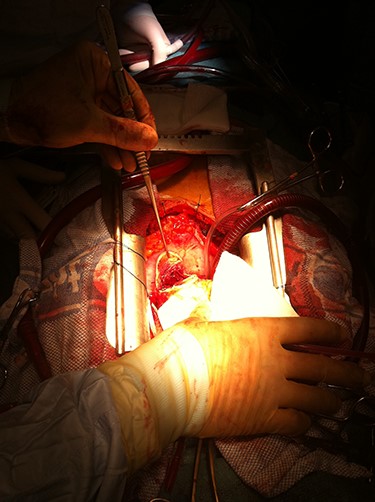

The heart was elevated following application of the cross-clamp and the 5-cm posterior aneurysm opened and the thrombus within removed completely (Fig. 4). The aneurysm was excised leaving a 1-cm rim of scar tissue, which was everted, and the defect closed in a linear fashion with double-layered, Teflon-buttressed, 3.0 Prolene sutures (Johnson&Johnson® Medical Devices). The heart was placed in the normal position and the left internal mammary artery was grafted to left anterior descending artery and saphenous vein graft to circumflex artery territory (obtuse marginal 1). An oblique aortotomy was performed; the stenotic aortic valve was excised, and a bioprosthesis was implanted. Post-operatively, systolic function was good together (LVEF 40%) with a well-seated aortic valve showing no paravalvular leaks. The patient was discharged home on the ninth post-operative day with dual antiplatelet therapy but no formal Coumadin-based anticoagulation as this was felt to incur too high a bleeding risk. This was a joint decision between both clinical teams and patient.

Intraoperative image demonstrating dissected LVA exposed and incised to perform intra-cavity thrombectomy.